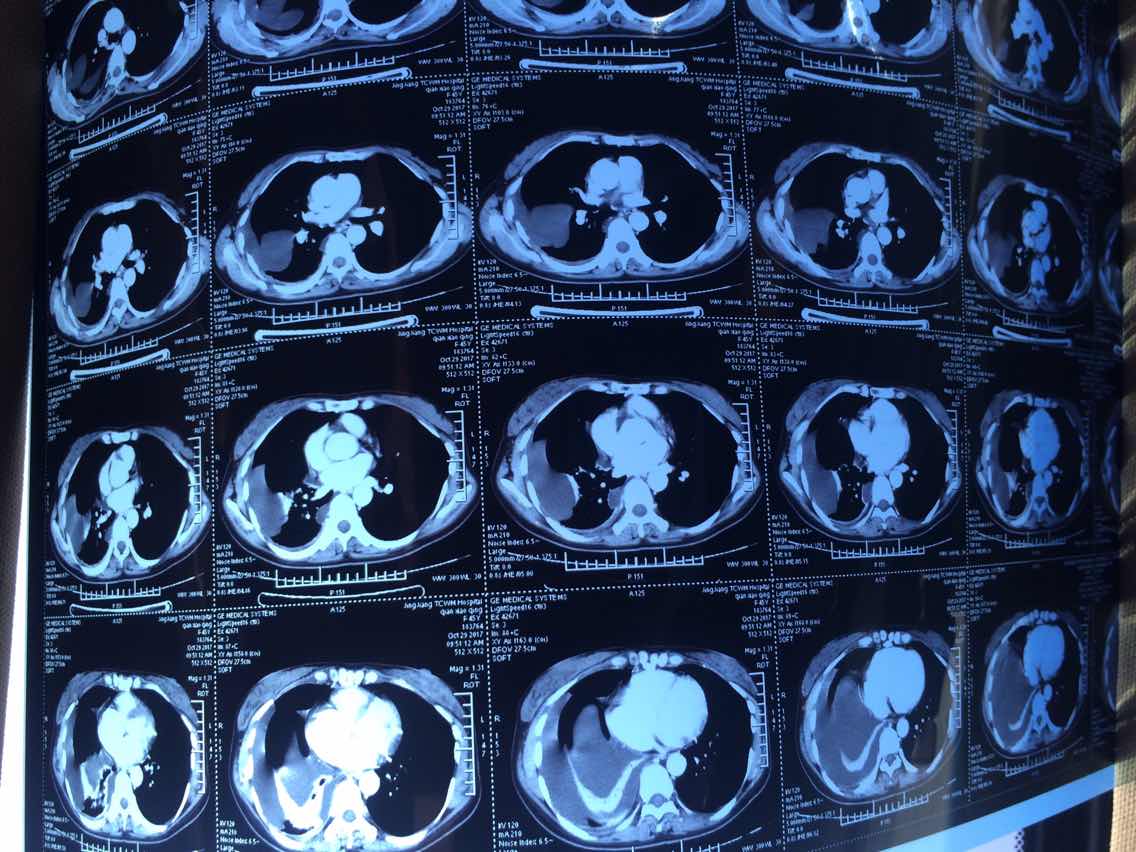

服易瑞沙11个月,很幸运,肿瘤pr。最近爱人体感比较差,可能快耐药了。昨天做了ct发现一轻微骨转,进入局部进展期。

2017.10.29ct

2017.10.29